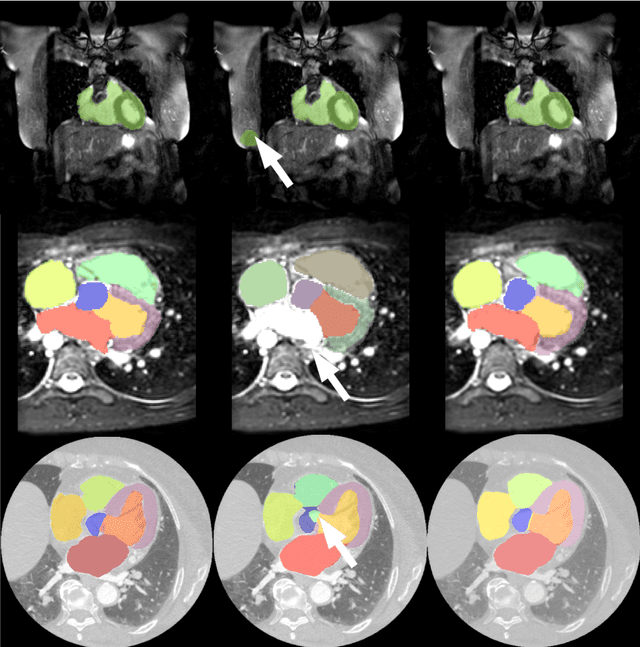

Abstract:Magnetic resonance (MR) protocols rely on several sequences to properly assess pathology and organ status. Yet, despite advances in image analysis we tend to treat each sequence, here termed modality, in isolation. Taking advantage of the information shared between modalities (largely an organ's anatomy) is beneficial for multi-modality multi-input processing and learning. However, we must overcome inherent anatomical misregistrations and disparities in signal intensity across the modalities to claim this benefit. We present a method that offers improved segmentation accuracy of the modality of interest (over a single input model), by learning to leverage information present in other modalities, enabling semi-supervised and zero shot learning. Core to our method is learning a disentangled decomposition into anatomical and imaging factors. Shared anatomical factors from the different inputs are jointly processed and fused to extract more accurate segmentation masks. Image misregistrations are corrected with a Spatial Transformer Network, that non-linearly aligns the anatomical factors. The imaging factor captures signal intensity characteristics across different modality data, and is used for image reconstruction, enabling semi-supervised learning. Temporal and slice pairing between inputs are learned dynamically. We demonstrate applications in Late Gadolinium Enhanced (LGE) and Blood Oxygenation Level Dependent (BOLD) cardiac segmentation, as well as in T2 abdominal segmentation.